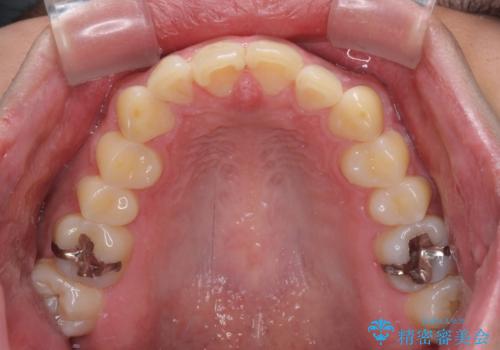

- 上下前歯のデコボコを気にして来院された患者様です。

前歯のデコボコ以外に左側の奥歯の咬み合わせに問題がありましたが、価格を抑え、短期間で気になる前歯を治したいとのことでした。

こちらの患者様は、事前のシミュレーションにより、インビザライン・ライトでは前歯のデコボコを解消しきれないことが分かったため、通常のインビザライン(コンプリヘンシブパッケージ)での治療が必要となりました。

しかし、費用面や期間で悩んでいらっしゃったため、左側臼歯の問題は解決せずに前歯のデコボコのみを改善するシミュレーションを作成し、治療を行うこととしました。